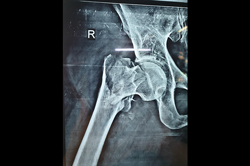

Neck Femur Fracture